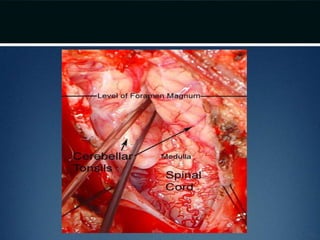

Posterior fossa decompression..

• Prone position and neck flexed

• Incision from below inion to the spinous process of

C2

• Avascular plane (nuchal ligament) b/t paraspinous

muscles followed down to bone and subperiosteal

dissection performed

• Moderate suboccipital craniectomy, width of the

foramen magnum followed by removal of posterior

arch of atlas

• Dura opened

• Arachnoid adhesions obstructing flow

removed and the floor of the 4th ventricle

examined

• Portion of occipital pericranium harvested

through a separate incision and duroplasty

performed